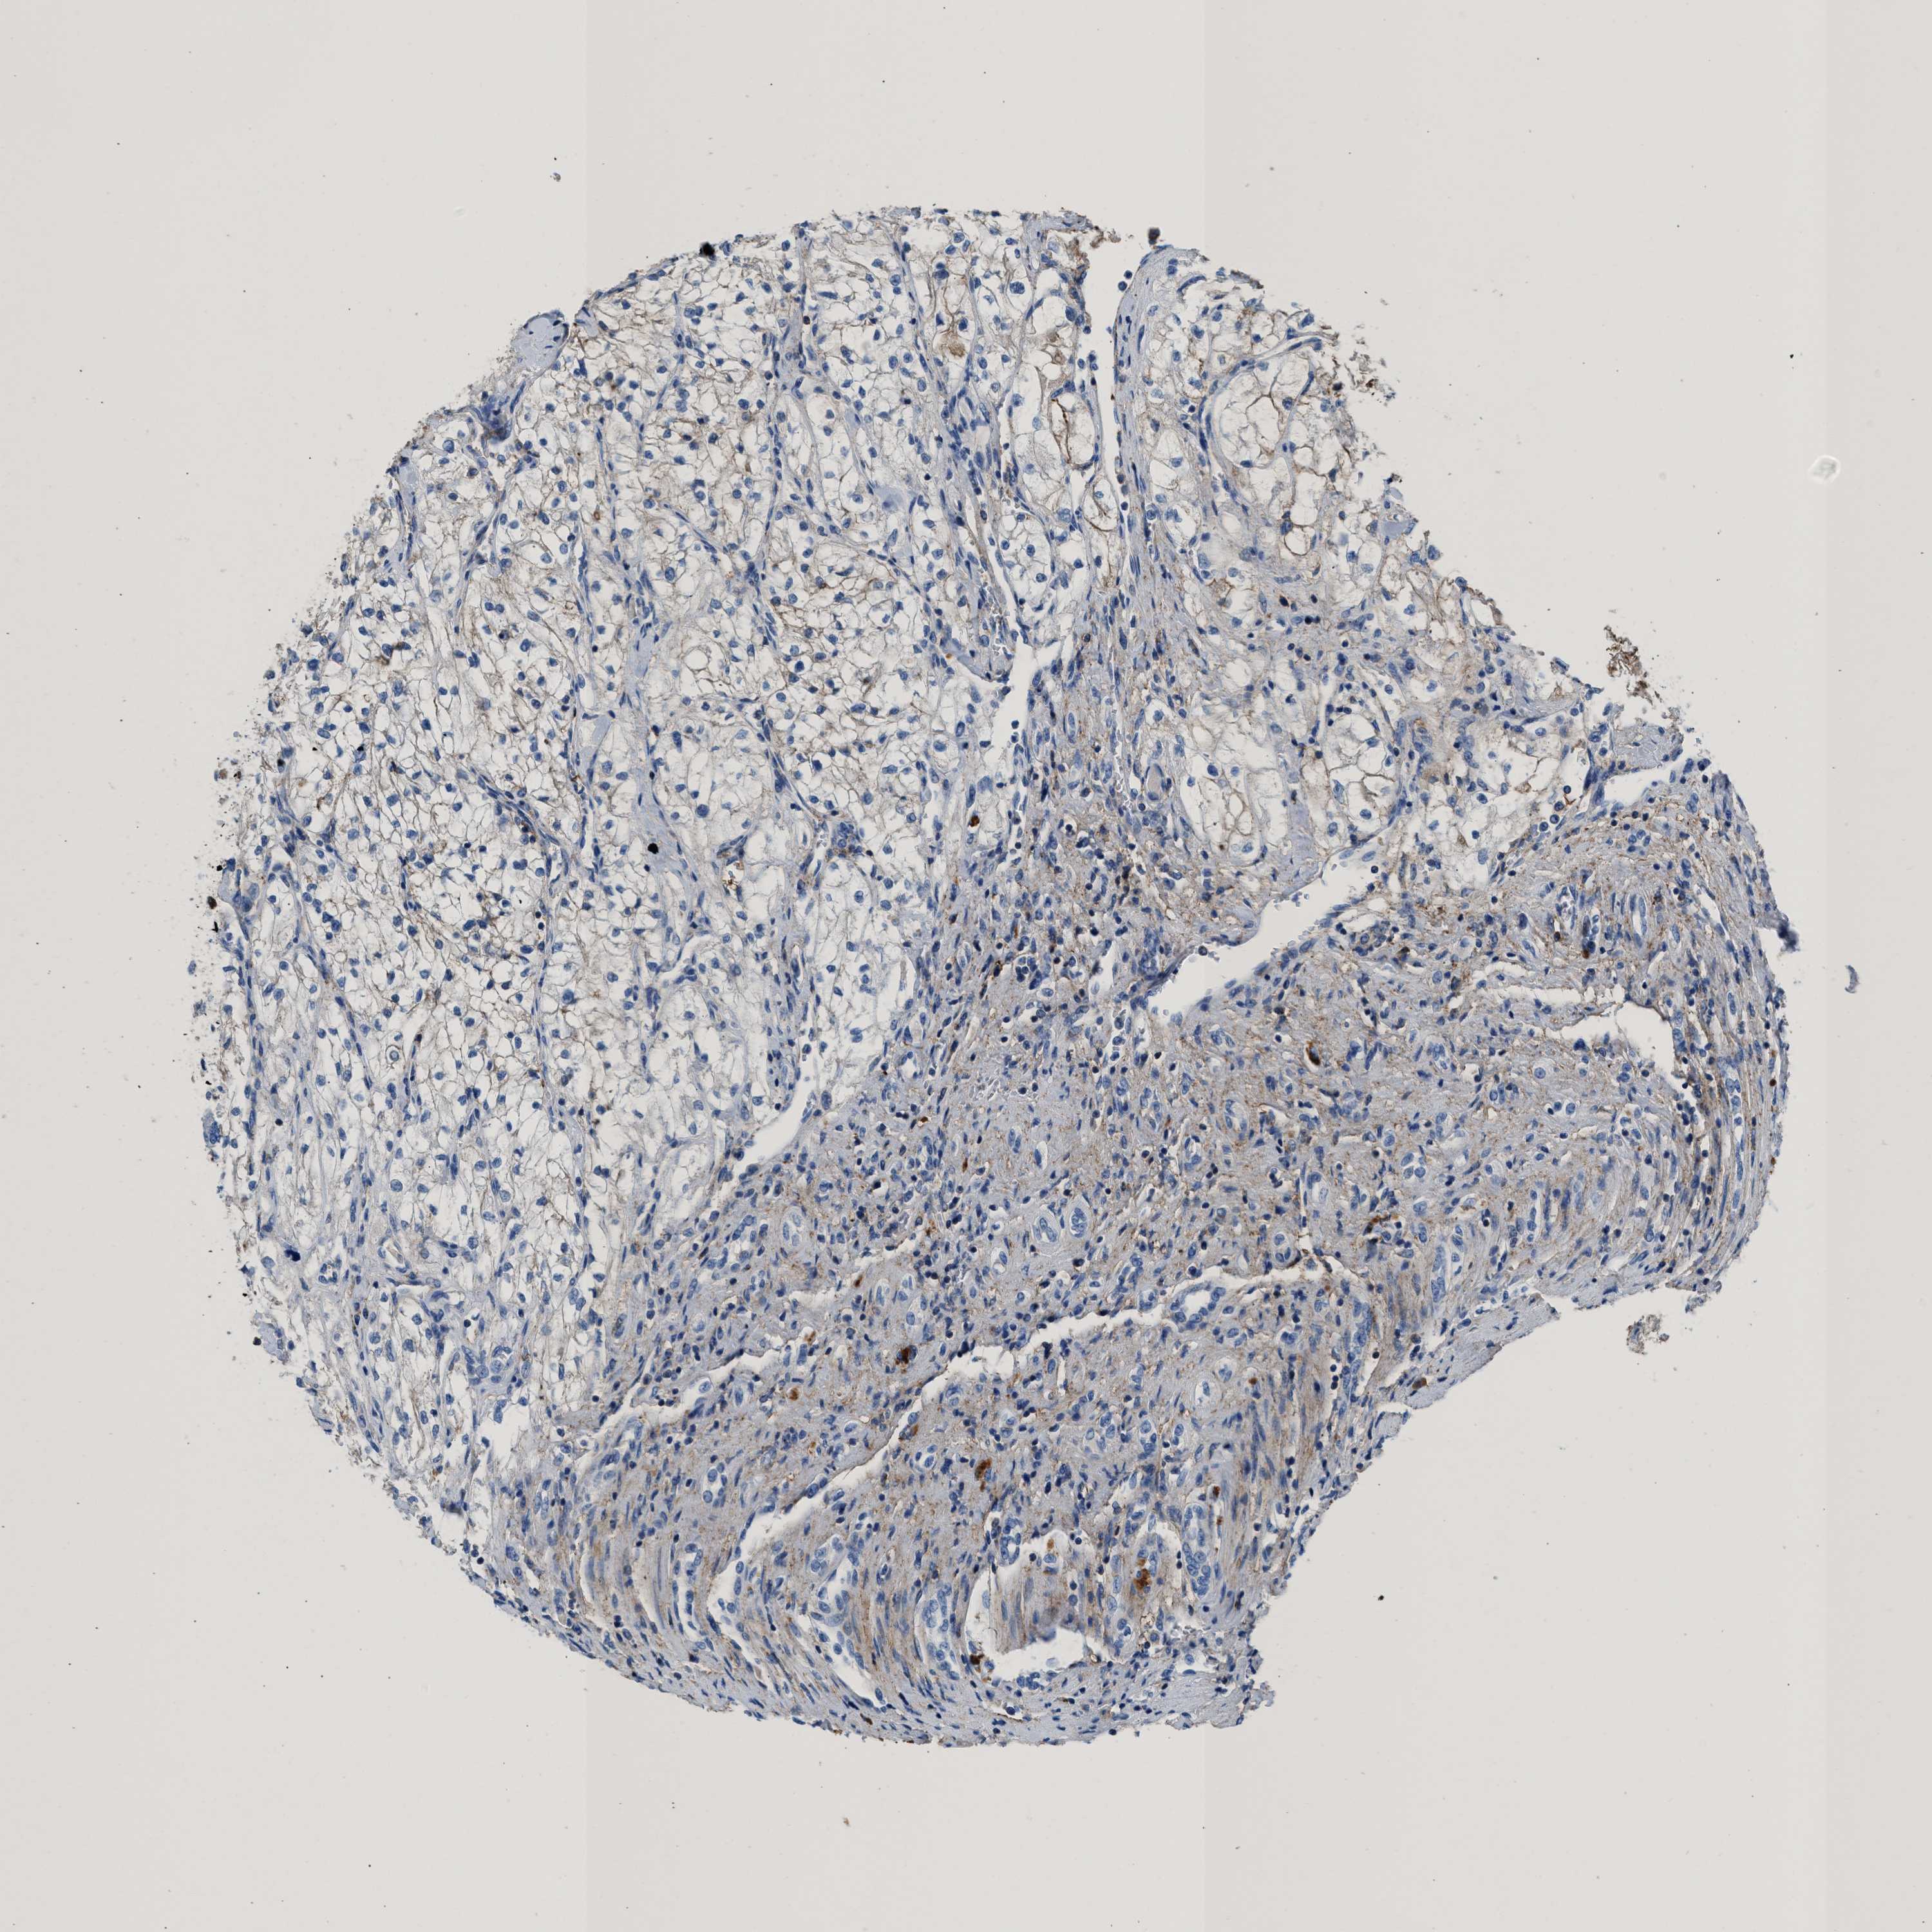

KIDNEY RENAL CLEAR CELL CARCINOMA (VALIDATION) - Interactive survival scatter ploti

The Survival Scatter plot shows the clinical status (i.e. dead or alive) for all individuals in the patient cohort, based on the same data that underlies the corresponding Kaplan-Meier plots. Patients that are alive at last time for follow-up are shown in blue and patients who have died during the study are shown in red.

The x-axis shows the expression levels (FPKM) of the investigated gene in the tumor tissue at the time of diagnosis. The y-axis shows the follow-up time after diagnosis (years). Both axes are complimented with kernel density curves demonstrating the data density over the axes. The top density plot shows the expression levels (FPKM) distribution among dead (red) and alive patients (blue). The right density plot shows the data density of the survived years of dead patients with high and low expression levels respectively, stratified using the cutoff indicated by the vertical dashed line through the Survival Scatter plot. This cutoff is automatically defined based on the FPKM cutoff that minimizes the p-score. The cutoff can be changed by dragging the vertical line or by entering a cutoff value in the square labeled "Current cut-off".

Under the Survival Scatter plot the p-score landscape (black curve; left axis) is shown together with dead median separation (red curve; right axis). Dead median separation is the difference in median mRNA expression between patients who have died with high and low expression, respectively. It is calculated as follows: median FPKM expression of dead patients with high expression - median FPKM expression of dead patients with low expression. This is intended to aid the user in visually exploring custom cutoffs and the associated p-scores and dead median separation.

Individual patient data is displayed and can be filtered by clicking on one or more of the category buttons on the top of the page. Categories describing expression level and patient information include: high, low, alive, dead, female, male and tumor stages. The scale of the x-axis can be toggled between linear and log-scale by clicking on the "x log" button. Mouse-over function shows TCGA ID, patient information and mRNA expression (FPKM) for each patient.

& Survival analysisi

Kaplan-Meier plots summarize results from analysis of correlation between mRNA expression level and patient survival. Patients were divided based on level of expression into one of the two groups "low" (under cut off) or "high" (over cut off). X-axis shows time for survival (years) and y-axis shows the probability of survival, where 1.0 corresponds to 100 percent.

KCNQ4 is not prognostic in Kidney Renal Clear Cell Carcinoma (validation)

TCGA RNA samplesi

RNA-seq data is reported as average FPKM (number Fragments Per Kilobase of exon per Million reads), generated by the The Cancer Genome Atlas (TCGA) .

Normal distribution across the dataset is visualized with box plots, shown as median and 25th and 75th percentiles. Points are displayed as outliers if they are above or below 1.5 times the interquartile range. FPKM values of the individual samples are presented next to the box plot.

Average pTPM 0.3

Number of samples 100